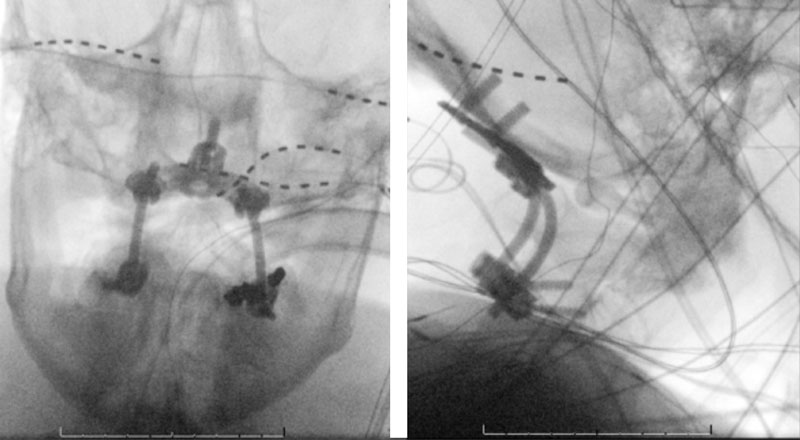

The patient was brought to the operating room, and general tracheal anesthesia was initiated via fiberoptic approach. Somatosensory potentials, motor evoked potentials, and brainstem auditory evoked responses were recorded. The patient then underwent intraoperative angiography of the right Vertebral Artery performed via a 5 French Right Radial Artery access. Once it was established that he had good flow, a Mayfield head holder was attached to the patient’s head on the 60 pounds of torque pressure. The Wilson frame attached to the Jackson table was then placed on top the patient attached to the Jackson frame. The patient was secured with straps and bed sheets and then positioned prone by rotating the frame around its axis. The flat plate of the Jackson table was then removed, and the patient bony prominences and soft tissues were adequately padded. Angiography was then again repeated showing good flow through the Vertebral Artery. After that, after being properly secured to the table with access to the right radial sheath, the neck and the left posterior iliac crest area and a tricortical autograft was then obtained with osteotomes. Iliac crest was reconstructed with fiber graft allograft. Posterior cervical incision was then performed and the spinous processes of C2 and C3 were identified and cleared of the fascia and then the muscle the way to the lateral edges of lateral masses. The C1 posterior ring was completely subluxed under the occiput and C2 lamina. The patient evoked potentials remained stable. The C1 lamina was then cleared of the soft tissue laterally on both sides. On the left side, significant osteophyte formation was visualized, and the C1-2 foramen was completely closed by the bone. On the right side, the C1-2 foramen was dissected, and the veins were coagulated with bipolar cautery. The C2 nerve root was identified and then coagulated bipolar cautery and divided with micro scissors, completing the planned C2 rhizotomy. The decision was made to perform an occiput to C3 fusion, since the articulation between the occiput, C1, and C2 was technically difficult and most likely would result in an inadequate fixation. At that point, a small occipital plate was brought into the field, and secured to the suboccipital bone with 14- and 12-mm screws. Then a pilot hold was created into the lateral masses of C3 bilaterally. The C3 appeared to be solidly fused to C2. First a hole was made with the drill and then passes were made with 40 mm drill with the guide. There were palpated with a ball-tipped probe and tapped. After the replaced 14 mm lateral mass screws into the lateral masses of C3 bilaterally. After the rods were fashioned and secured to the screw heads and the occipital plate with locking caps. (Figure 6)

Intraoperative angiography was then repeated again, showing good flow through the right Vertebral Artery into the Basilar Artery. Intraoperative fluoroscopy was then also performed to confirm good position of the screws and rods in both AP and lateral projections. (Figure 7)